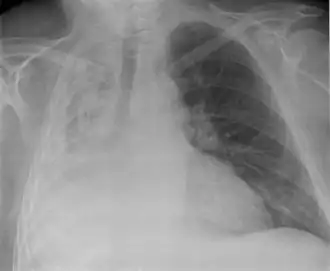

![]() Тотальный ателектаз правого лёгкого (вид спереди) | |